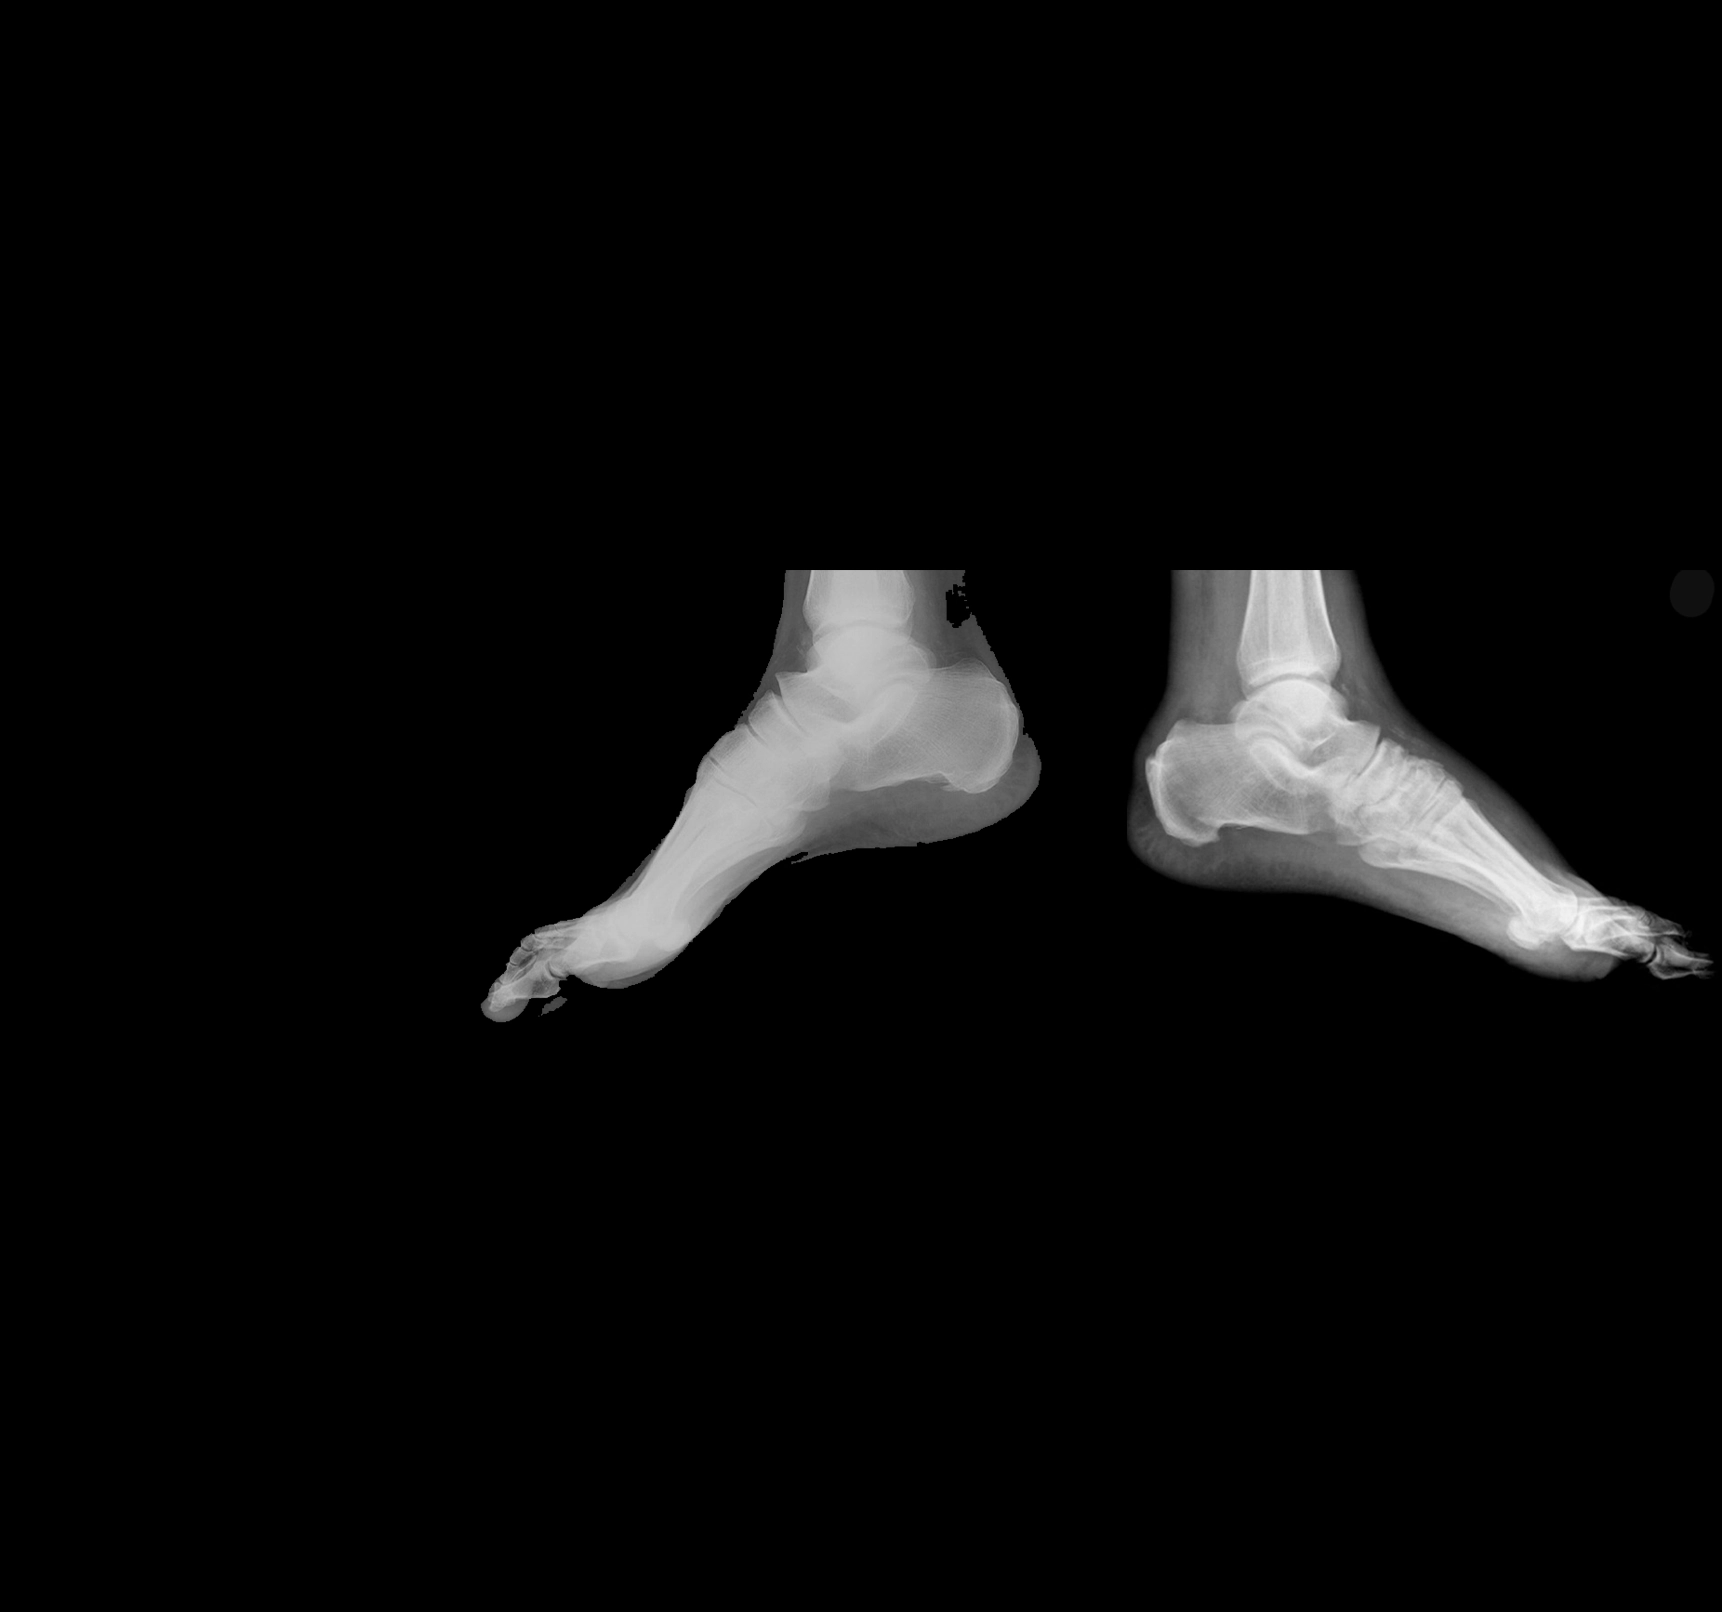

What is Charcot Arthropathy? Symptoms and Treatment Methods